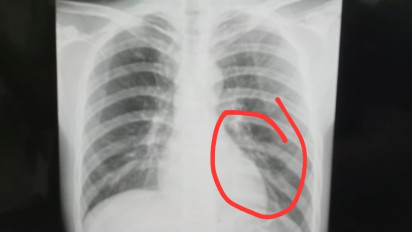

pemain Perseta Tulungagung bernama Firman Nugraha mengalami cedera serius berupa retak tulang dada

Akibat insiden tersebut, pemain Perseta Tulungagung bernama Firman Nugraha mengalami cedera serius berupa retak tulang dada dan dipastikan absen dalam dua pertandingan berikutnya.